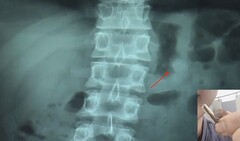

Medical staff took an X-ray image that showed the AirPod sitting in the recruiter’s stomach, in what seemed like quite a snug fit. Hsu was given laxatives and a later call of nature at a railway station ended with the “lucky” man being reunited with his digested AirPod. Whether or not you find the next part of the story gross will likely depend on how much of an Apple fan you are: Mr. Hsu proceeded to clean and dry the AirPod and then tested it to see if it still worked, which it did, and it even still had 41% of its battery remaining.